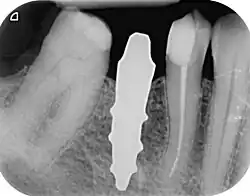

RAIs are custom made to perfectly fit the tooth socket of a specific patient immediately after tooth extraction. Therefore every implant is unique. As an optimised root-form it is much more than a simple 1:1 replica of a tooth. Since it exactly fills the gap left after the tooth is extracted, surgery is rarely needed. The implant can be produced from a copy of the extracted tooth, an impression of the tooth socket, or from a CT scan or CBCT scan.[7] The advantage of a CBCT scan is that the implant can be produced before extraction. With the former methods, it takes one or two days to fabricate an implant.

A root analogue implant can be fabricated from zirconium dioxide (zirconia) or titanium.[8] Successful titanium RAIs have been three-dimensionally printed as porous one-piece implants, using CAD software.[9] However, zirconia is the preferred material, because it is more esthetic in colour, with no grey discolouration visible through gums.[10][5]

- Natural form: a custom milled anatomic implant replicates the natural form of a tooth, so it simply fits into the tooth socket. Like the original tooth, a root analogue implant can have single- and multi-rooted forms.